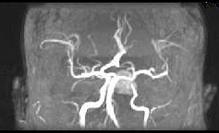

- 单项选择题男性,55岁, 头痛一年余,两个小时前突然出现剧烈头痛, MRI检查如图所示,最可能的诊断为 ( )

E、动脉瘤